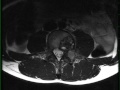

Aneurysmal Bone Cyst, secondary to osteoblastoma

12-year-old male with left lower back pain. There is an expansile T1-isointense mass centered on the left pedicle of vertebra L4. There is isointense soft tissue which extends into the epidural space. There is also invasion of the left posterior aspect of the L4 vertebral body, left L4 lamina, and transverse process of L4 on the left. On the STIR-weighted images, the lesion is heterogeneous in signal intensity, with regions of hypo-, iso-, and hyperintense signal. On the axial STIR-weighted images, there are subtle dependent fluid/debris levels. There is also evidence of hemosiderin deposition along the margins of the lesion. The differential includes primary aneurysmal bone cyst (ABC), telangiectatic osteosarcoma, and secondary aneurysmal bone cyst. Secondary causes include giant cell tumor, chondroblastoma, osteoblastoma, and fibroxanthoma. This is an ABC in a giant osteoblastoma. ABCs represent variable-sized hemorrhage filled spaces separated by connective tissue. Up to 1/3 of ABCs are of the secondary type. The most common locations include long bones, spine/sacrum, craniofacial and epiphyses.